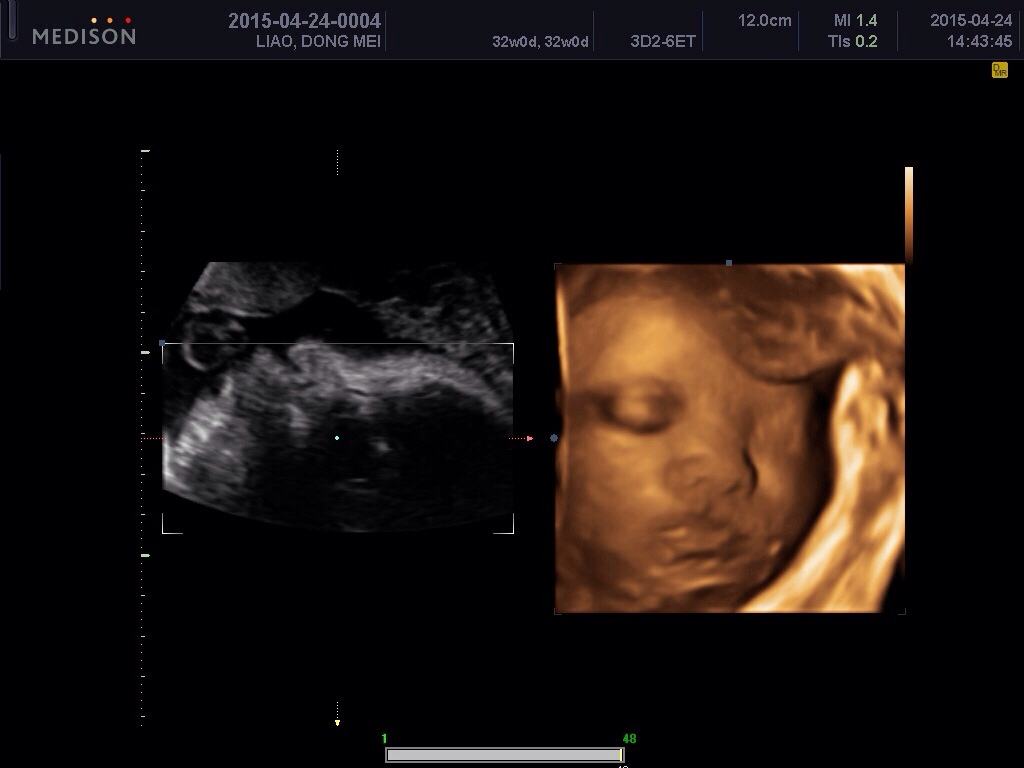

四维彩超就像我们平时看的3D电影一样,让医生看到子宫内胎儿更为直观、立体的影像。大部分的胎儿四维照显得很丑,或者嘴巴大鼻子大,原因有以下三点。

毕竟四维彩超目的是排畸,医生通过全方位及多切面扫孕妈的腹部,区别测量获得宝宝的头围、双顶径侧面、眼眶横切面、唇冠状、左右室流出道切面等等,所以医生会选择放大这部分的特征以仔细查看,顺便就把胎儿的面部特征拍下来了,“送”给父母。非专业人士就看到宝宝的嘴巴和鼻子特别大,所以比较奇怪。

胎儿在子宫内被羊水包裹,而且将自己的部分排泄废物排到羊水中去,胎儿皮肤上会有一层胎脂,是来保护胎儿肌肤不受羊水伤害的。而胎脂的表面并不光滑,而且并不是均匀分布在皮肤上,若是嘴巴鼻子周围胎脂较多,再加上羊水的放大作用,就会显得胎儿的嘴巴和鼻子特别大。从四维照上可以看出,胎儿头面部位都是凹凸不平的状况,有人戏称好像外星人,那就是胎儿表面的胎脂。